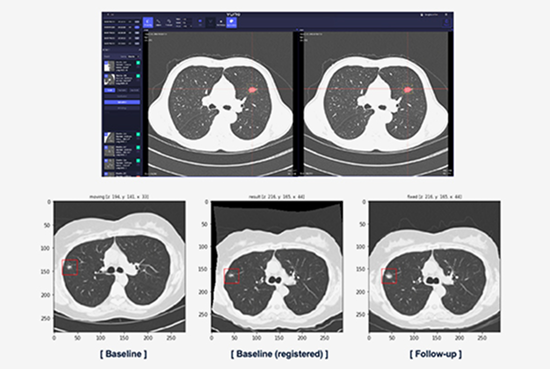

Longitudinal Tracking

•  Provides baseline scans and follow-up data for nodule growth assessment

•  Can match the baseline scan and follow-up scan pixel to pixel